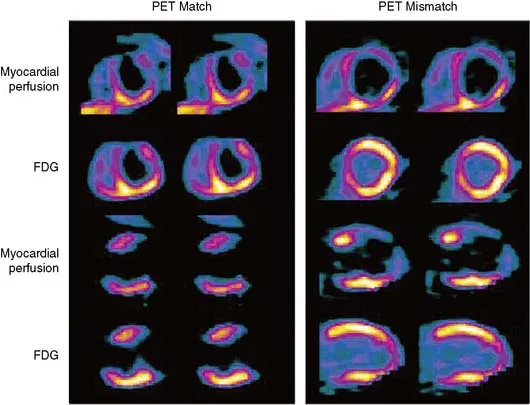

PET imaging delivers superior spatial resolution (4-5 mm vs. 10-15 mm for SPECT) and quantitative blood flow measurement, detecting coronary disease with 90-95% sensitivity. Rubidium-82 perfusion imaging combined with F-18 fluorodeoxyglucose (FDG) metabolism imaging identifies viable myocardium through perfusion-metabolism mismatch patterns.

| Perfusion | Metabolism | Interpretation | Viability | Revascularization Benefit |

|---|---|---|---|---|

| Normal | Normal | Normal myocardium | 100% viable | No benefit |

| Reduced | Normal/Increased | Hibernating myocardium | 80-90% viable | High benefit |

| Reduced | Reduced (matched) | Transmural scar | <50% viable | Low benefit |

| Normal | Reduced | Stunning (post-ischemic) | 90-100% viable | Moderate benefit |

| Reduced | Absent | Complete infarction | <10% viable | No benefit |

⭐ Clinical Pearl: PET viability imaging predicts functional recovery with 85% accuracy when perfusion-metabolism mismatch involves ≥10% of left ventricular mass, guiding revascularization in patients with severe LV dysfunction (ejection fraction <35%) where hibernating myocardium comprises 25-40% of dysfunctional segments.

💡 Master This: When SPECT shows fixed defects but viability remains uncertain, PET FDG imaging resolves the question-perfusion-metabolism mismatch in ≥5 segments predicts 80% probability of functional improvement post-revascularization, while matched perfusion-metabolism defects indicate scar with <20% recovery likelihood.